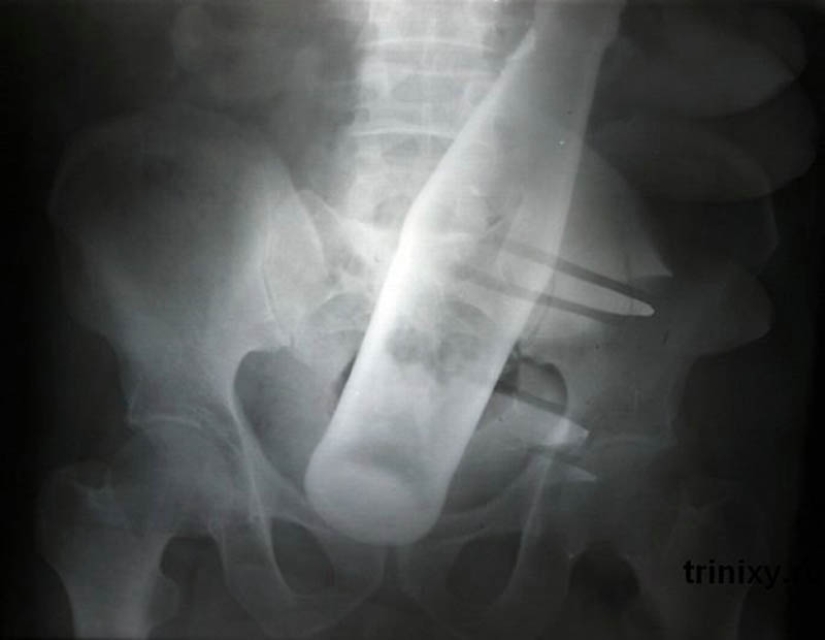

20. A Pepsi bottle in the anus of a 60-year-old man.